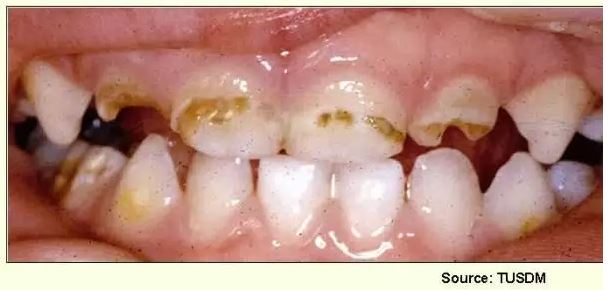

Tetratsükliini liigtarbimise tõttu värvunud hambad

Fluoroos

Emaili hüpoplaasiad

– Hammaste krooni kaltsifitseerumise häired, emaili hüpoplaasiad, on üsna sagedased. Need on nähtavad vahelduvate värvi- ja ehituse muutustena hamba pinnal.

– Hüpoplaasia on tingitud emaili tootvate rakkude normaalse talitluse häirumisest, mida tavaliselt

põhjustavad välised tegurid (näit. nakkused).